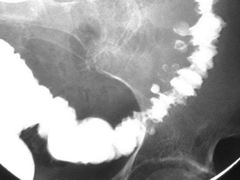

colorectal carcinoma found anywhere from the cecum to the rectum. most start out as a polyp. has an apple core radiographic appearance

colon cancer

Back